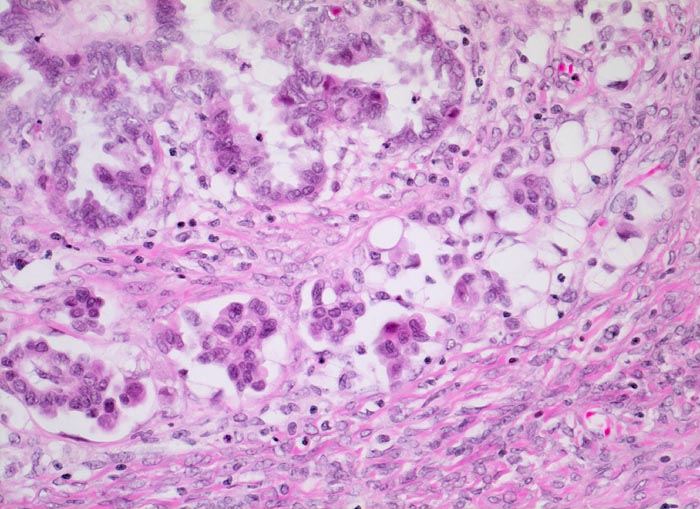

PathoPic ID 4479 - mikroinvasives serös papilläres Ovarialkarzinom

mikroinvasives serös papilläres Ovarialkarzinom

maligner Tumor

Ovar

Genitalorgane, weiblich

An umschriebener Stelle invadieren

kleinere Zellgruppen und

Einzelzellen das an dieser Stelle aufgelockerte Stroma.

Histologie

200

24